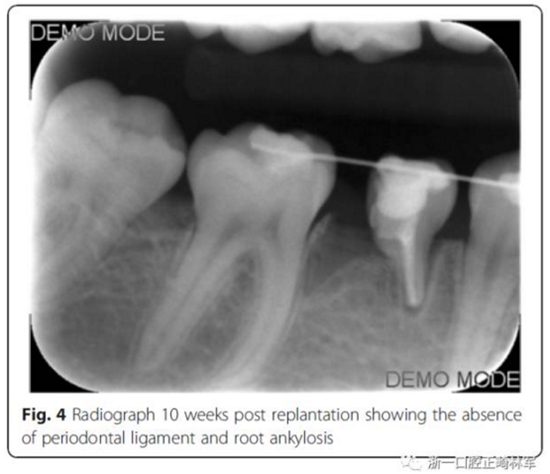

10周后,根據臨床和影像,形成乳磨牙牙槽粘連,移除牙弓夾板。下一步,在右下第一磨牙上粘接帶環(huán),在第二乳磨牙和下頜第一前磨牙上粘接托槽,在恒磨牙和乳磨牙之間安裝T型曲前移第一恒磨牙。T型曲共激活9次。